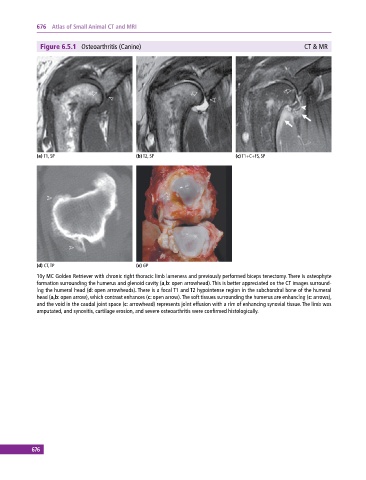

Figure 6.5.1 Osteoarthritis (Canine) CT & MR

(a) T1, SP (b) T2, SP (c) T1+C+FS, SP

(d) CT, TP (e) GP

10y MC Golden Retriever with chronic right thoracic limb lameness and previously performed biceps tenectomy. There is osteophyte

formation surrounding the humerus and glenoid cavity (a,b: open arrowhead). This is better appreciated on the CT images surround-

ing the humeral head (d: open arrowheads). There is a focal T1 and T2 hypointense region in the subchondral bone of the humeral

head (a,b: open arrow), which contrast enhances (c: open arrow). The soft tissues surrounding the humerus are enhancing (c: arrows),

and the void in the caudal joint space (c: arrowhead) represents joint effusion with a rim of enhancing synovial tissue. The limb was

amputated, and synovitis, cartilage erosion, and severe osteoarthritis were confirmed histologically.